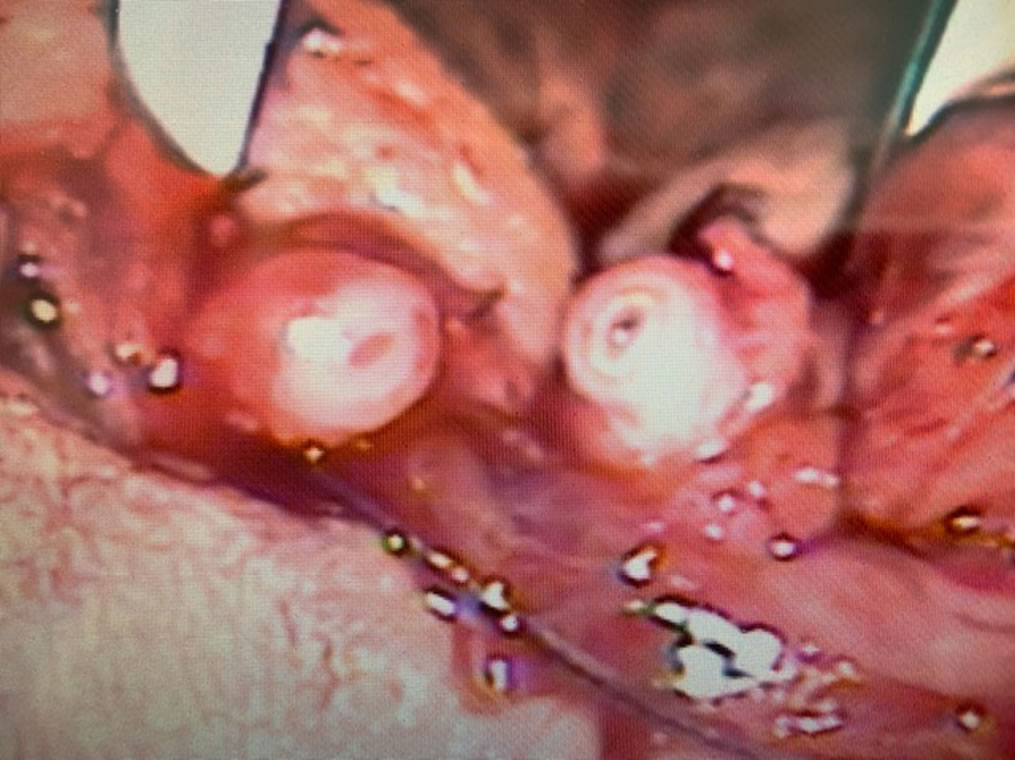

En esta foto con microscopio, se observan el deferente que viene del testículo y el deferente que va hacia la próstata. Ambos cabos los vamos a unir (anatomosar) para que los espermatozoides que se forman en el testículo vayan hacia la próstata y pueden ser expulsados con el semen durante la eyaculación.

Esta es la imagen final de la anastomosis, ambos cabos del deferente están unidos mediante microcirugía. Los espermatozoides van a pasar desde el testículo hacia próstata y en pocos meses se recupera la fertilidad.